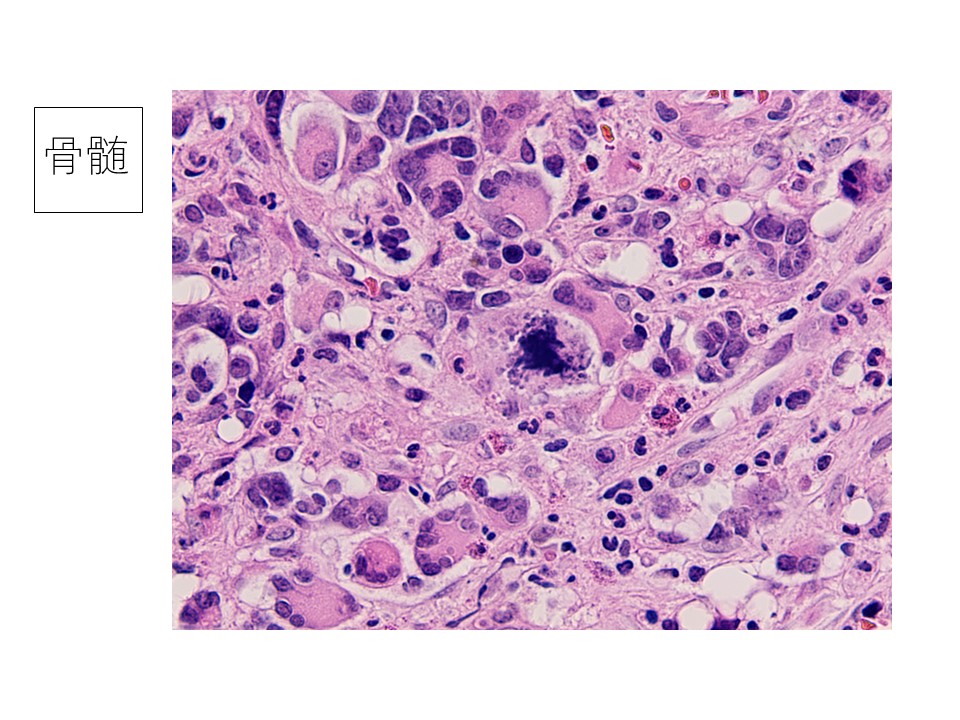

骨髄生検スタンプ:多核の大型異型細胞を散在性に認める。周囲には小型から中型の芽球様の細胞が出現している。大型細胞の細胞質の一部に細胞突起様の存在が疑われる。

骨髄組織:多核で多型性を示す大型細胞が散在し、奇怪な核分裂像を認める。免疫染色の結果FactorⅧとCD61がともに陽性で、急性巨核芽球性白血病と診断。

骨髄細胞の診断に苦慮した。縦隔腫瘍からの転移を考えていたが、細胞をよく観察すると巨核芽球に特徴的な所見(ブレブ:細胞突起)を認めたことから、血液疾患を指摘することは可能であったと思われる。